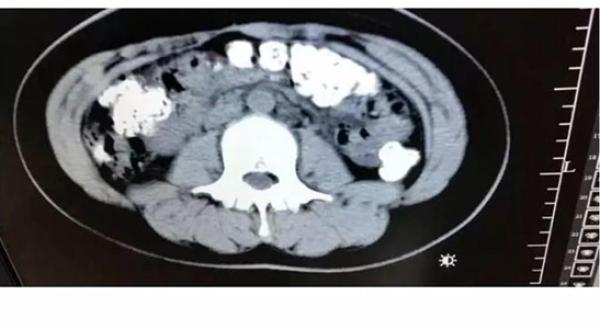

日前中國浙江一名14歲少女,因為多天沒有排便,腹部劇烈疼痛而急赴醫院求解方,沒想到經過儀器斷層掃描後,才發現這一切都是珍珠惹的禍,這名少女的腸胃,全部擠滿了一顆顆未消化的珍珠,足足有百顆!

一見到這樣的情形,醫師當然嚇壞了,詢問少女「最近有沒有吃過什麼不易消化的食物?」少女才回答「在五天前喝過珍珠奶茶」,不過醫生推斷,少女可能是怕被父母責罵才隱藏自己的病史,「因為這麼多未消化的珍珠,不像喝一杯珍奶就累積的,應該是喝了一段時間所造成的。